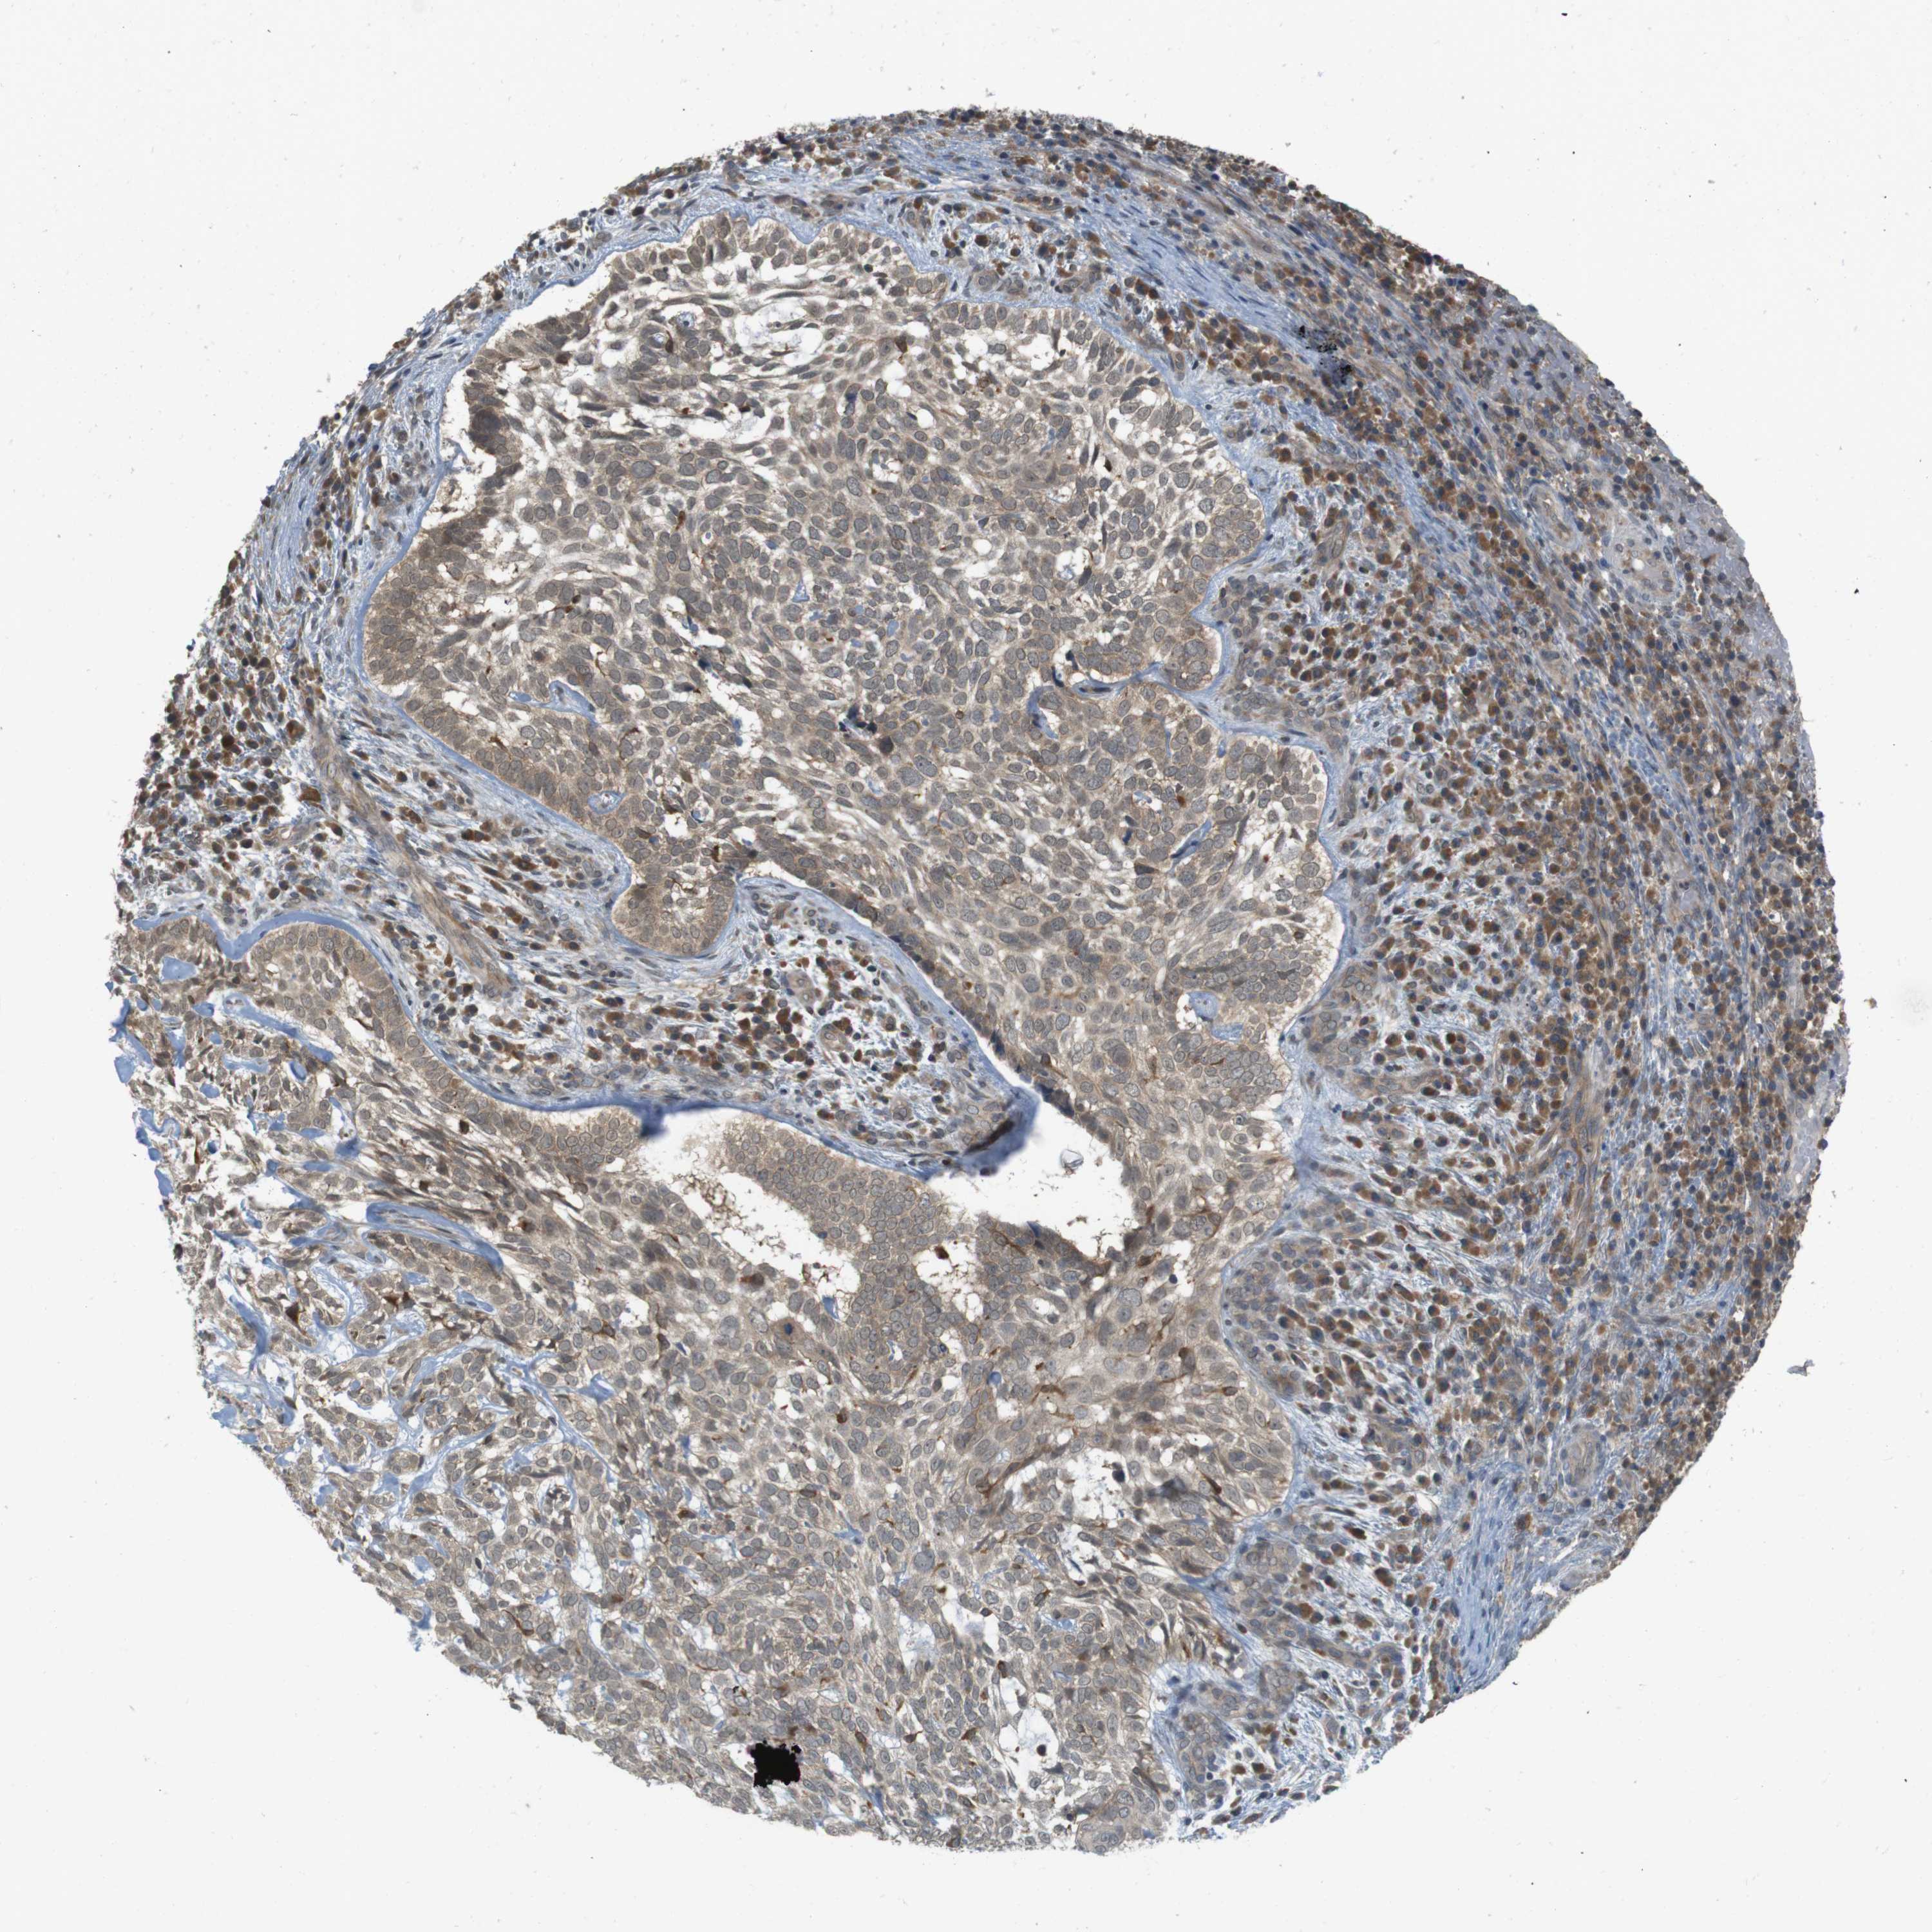

SKIN CANCER

Basal cell and squamous cell cancer